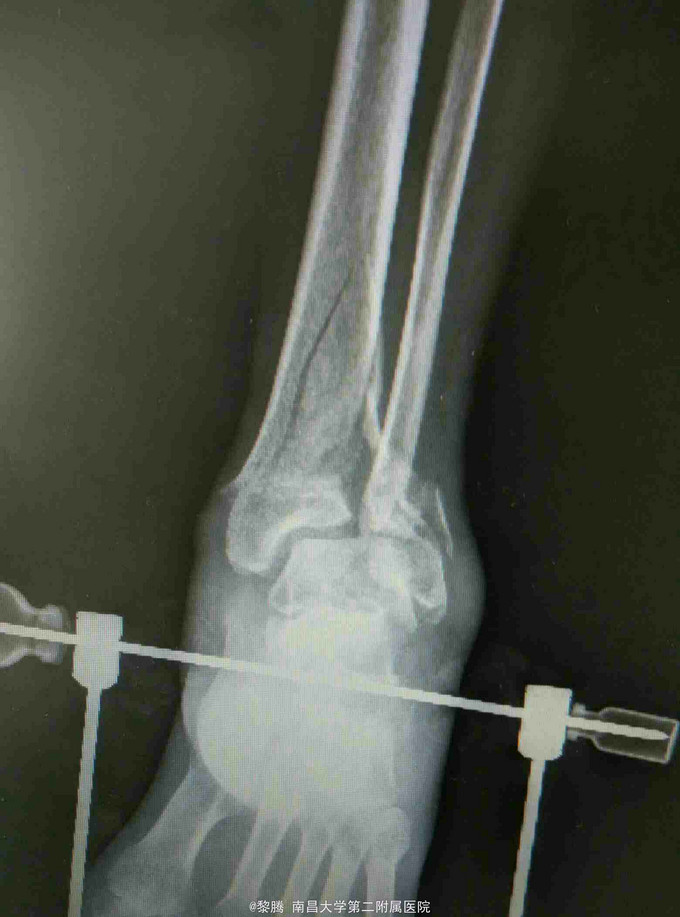

摔伤致左足肿痛,活动受限半天 患者中年男性,因不慎摔倒左足着地,出现左足肿胀疼痛,伴有明显活动受限,无开放性伤口患者伤后未诉明显左足感觉异常。伤后急诊入我院就诊。

查体:左足及左踝关节肿胀明显,局部压痛明显,局部皮肤可见张力性水泡,左踝关节活动受限明显,足背动脉搏动存在,无明显感觉异常。 辅查:踝关节正侧位片提示胫腓骨远端骨折

诊断:Pilon骨折 治疗:骨折切开复位内固定